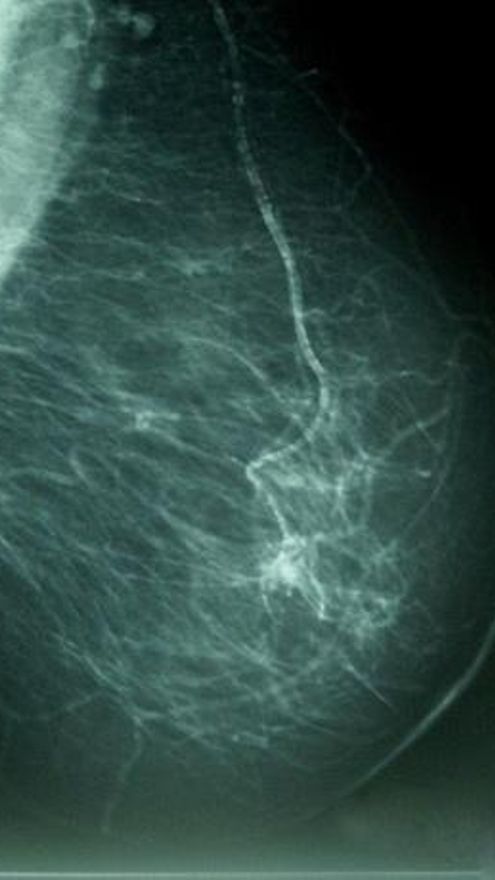

La decodificación del ADN permite identificar la firma genética del cáncer de mama

Descifrar el ADN de las pacientes con cáncer de mama avanzado, ha permitido a los científicos identificar distintas firmas genéticas del cáncer, que podrían ayudar a predecir qué mujeres tienen más probabilidades de beneficiarse de la terapia de reducción de estrógenos, según un hallazgo publicado en la revista 'Nature'.